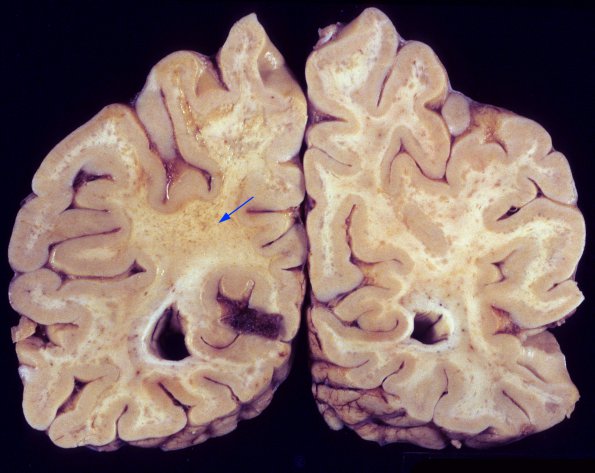

1A3,4 Heavily involved cerebral hemispheric white matter consists of both small patches of demyelination as well as large areas of confluent involvement (arrow).